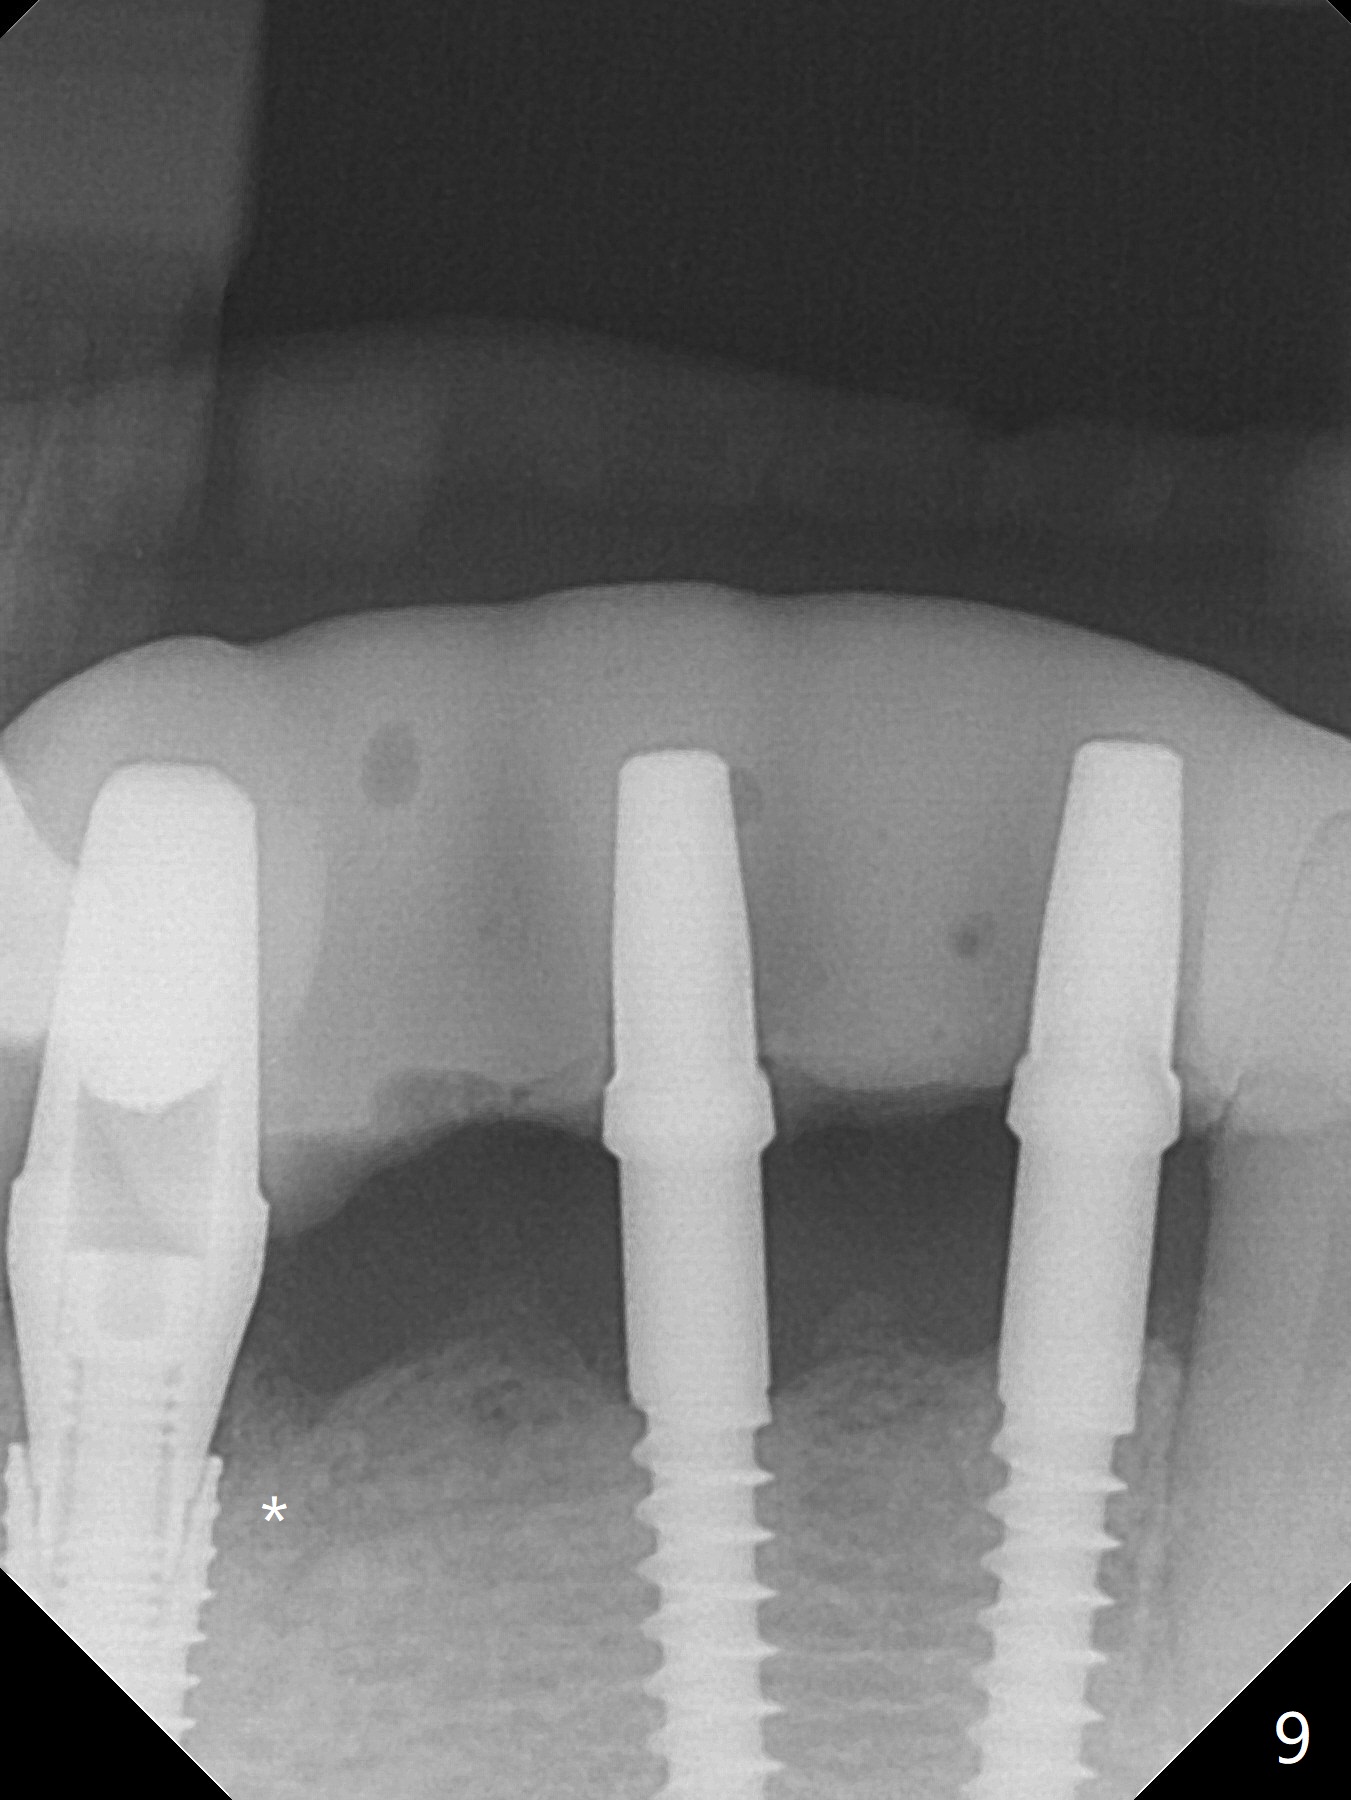

There is severe buccal gingival recession at #27 (Fig.1 arrow), as compared to that at #22. After removing the bridge and extraction of #27 (Fig.2 with severe loss of the buccal plate), a 3x18 mm drill is used to finish osteotomy (Fig.3). A 3.8x13 mm UF implant (Fig.3 green line) will be placed with 9 mm in the apparently solid, native (new) bone (blue line), while the coronal 5 mm will be occupied by the 5 mm cuff of a cemented abutment (pink line). The white dashed line is the gingival margin. The osteotomy is initiated as lingual as possible so that there will be at least 2 mm buccal gap when the narrow implant is placed. In spite of effort and precaution (guided surgery could control the trajetory), the coronal end of the implant tilts buccally so that a 4.5 mm 15 ° A 4 mm angled abutment is placed slightly subgingival (except buccal; Fig.5 A).

The mesial defect at #27 appears to have been repaired 8 months postop (Fig.8,9 *); there is no bone loss at 1-piece implant sites. The gingival recession seems to remain the same before and after removal of the provisional FPD (Fig.10,11). The bulging abutment at the cervix is less prominent when a straight abutment is used and prepared (Fig.12, 4.5x5.5(5) mm). There is no bone loss at #23, 25 and 27 sites 2.5 years post cementation (Fig.12-15), although the trajectory of the implants could be improved by using surgical guide (Fig.16-18).